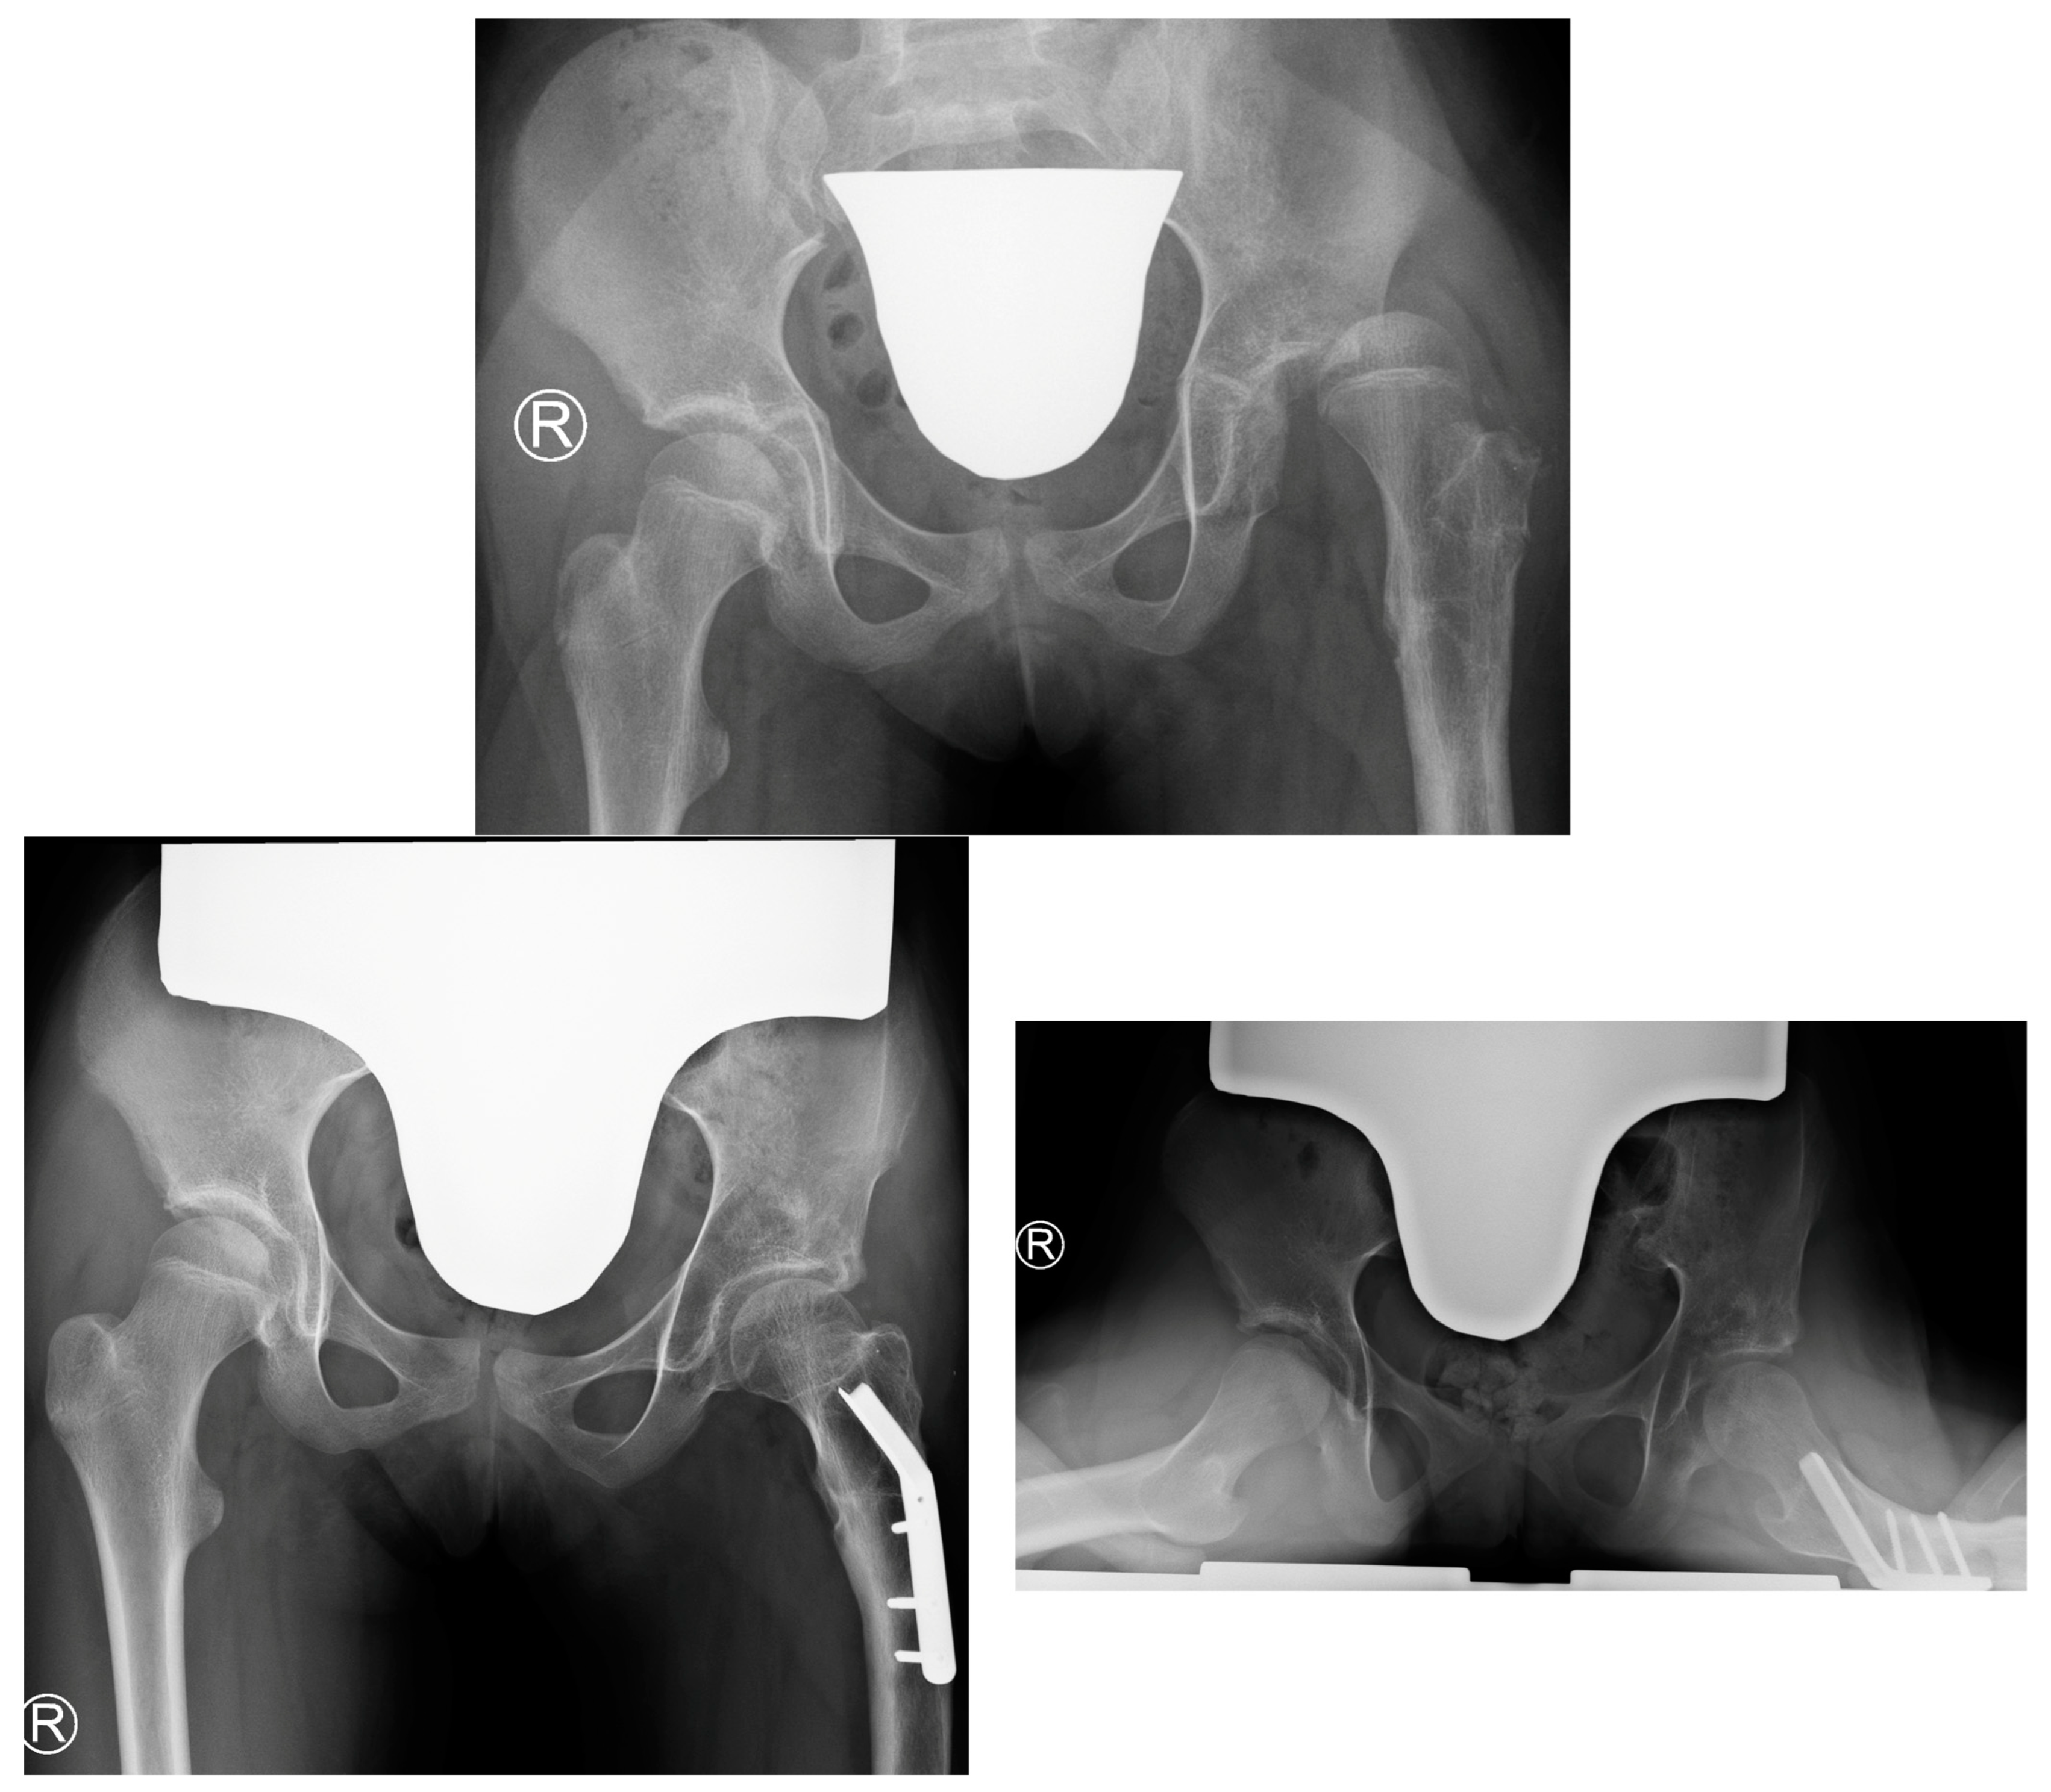

The key clinical information about hip instability cases is summarized in Table 9. Figure 4 shows radiograms and CT scans of the case of hip joint instability after femoral lengthening (Case 2).

Figure 4.

Patient with hip joint instability after femoral lengthening. The first row shows radiograms at initial evaluation with diminished antetorsion on the right radiogram. The second row shows radiograms after hip preparatory surgery. The third row shows radiograms after removal of the external fixator (left side) and after treatment of the femoral fracture—Rush rod with external fixator (right side). The fourth row shows radiograms the first post-op day after removal of the Rush rod, with visible left hip joint dislocation. The final and fifth row shows radiograms 1 year after surgical treatment—the left hip joint remained stable (last follow-up—over 4 years post-surgical treatment of dislocation).